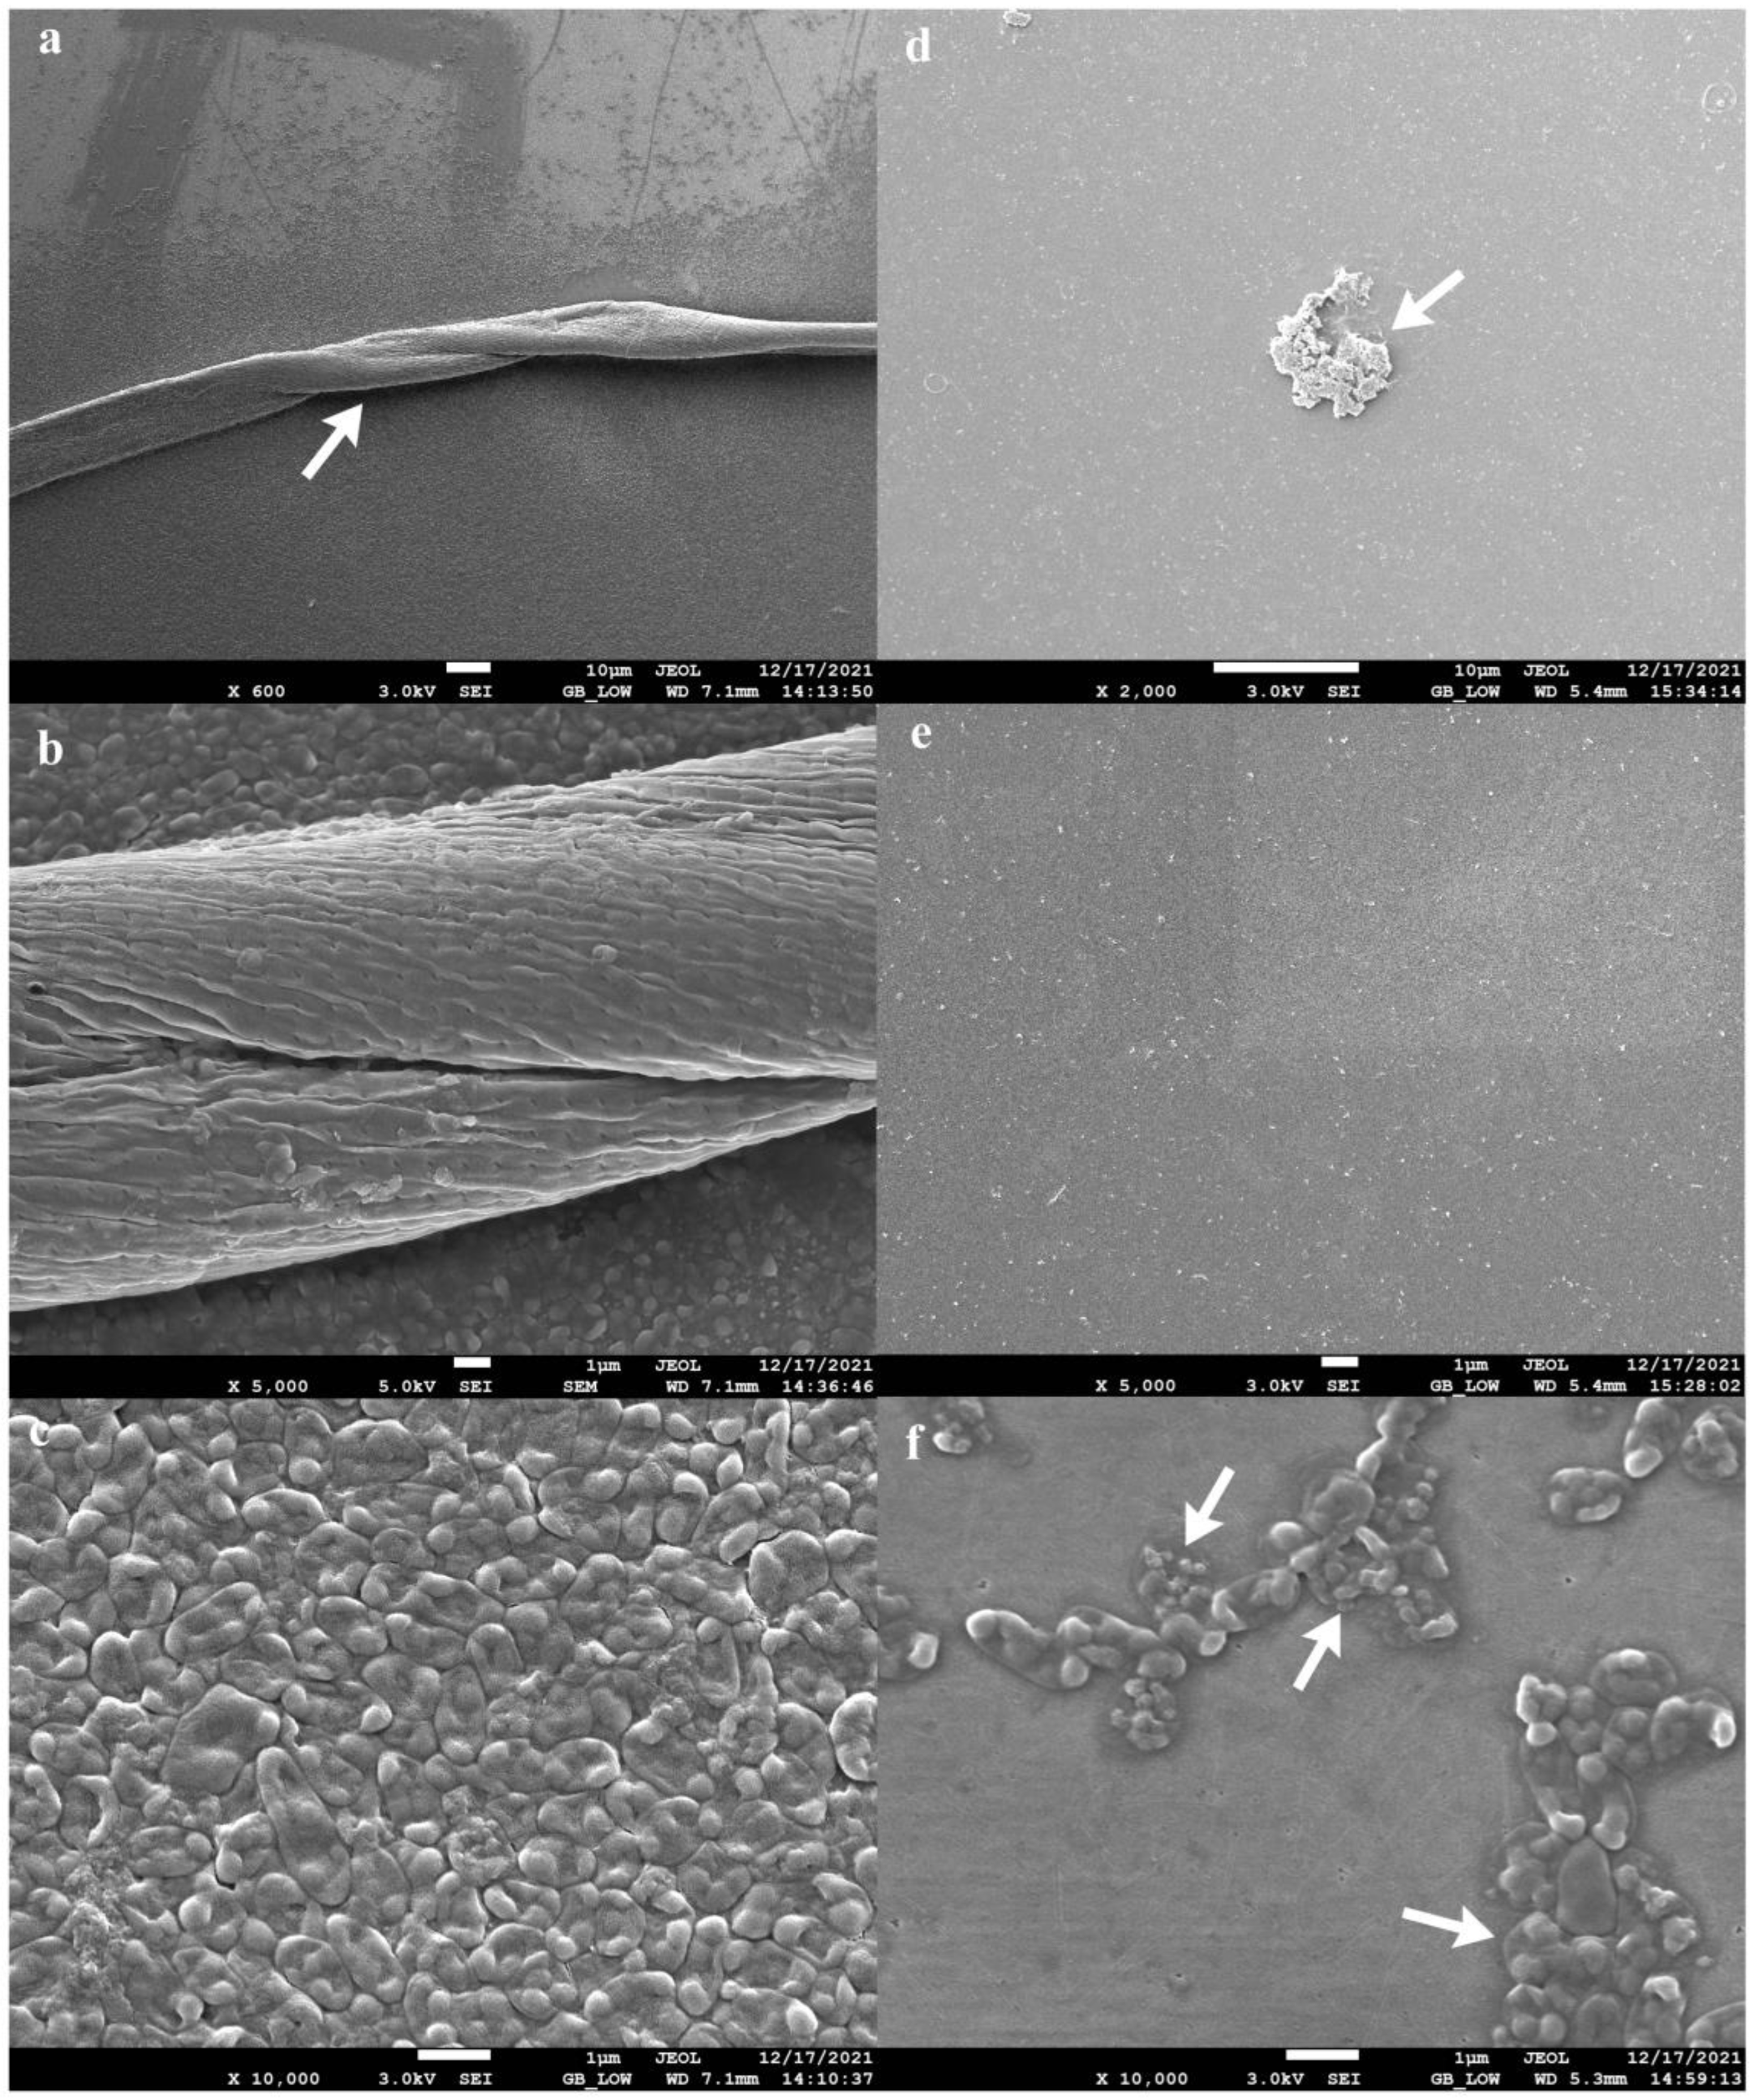

The four-phage cocktail (φPA170 + φPA172 + φPA177 + φPA180), which resulted in the strongest inhibition of XDR P. aeruginosa strain was tested for its biofilm eradication ability. The 96-hour-old biofilms, developed on urinary catheters and glass cover slips, were used to demonstrate phage cocktail-mediated eradication. The biofilms developed on the inner walls of urinary catheter are indicated with prominent features such as multilayered protrusions of varying height and density arising from underlying layers of cells (Figure 6a). The core of the biofilm was also visible through breaks in the biofilm structure (Figure 6b). Cells adhering together and to the surface of the catheter in the gelatinous matrix of EPS could be seen (Figure 6c). After treatment with the bacteriophage cocktail, eradication of the biofilm (Figure 6d–f) was clearly noticeable without the presence of any intact cellular structure, and it was further confirmed by viable cell count using CFU assay. On cover slips, swivelled cords of P. aeruginosa cells compactly adhered together, and could be seen running through the biofilm structure (Figure 7a,b). Tightly packed cells of P. aeruginosa in monolayers could also be appreciated (Figure 7c). After the treatment, the surface of cover slips with eradicated biofilm (Figure 7d,e) and burst cell debris (Figure 7f) were visible.

Biofilm eradication ability of phage cocktail comprising φPA170, φPA172, φPA173, and φPA180. Panels (a–c) represent 4-day-old biofilms developed on the borosilicate glass cover slips. Swivelled cords as indicated by arrows (a,b) and monolayers (c) of compactly adhered P. aeruginosa cells can be observed. Panels (d–f) represent eradicated biofilms and burst cell debris (indicated by arrows) after treatment with bacteriophage cocktail for 12 h. Biofilms were visualized in a JSM-7610F Plus Scanning electron microscope, Jeol, Akishima, Japan, after glutaraldehyde fixation and ethanol gradient dehydration.